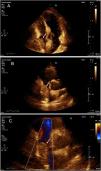

A: Transthoracic echocardiography showing echo-dense mass of 32 mm×31 mm, area 9.8 cm2 within right atrium suggestive of mass or intracavitary thrombus (white arrow). C: Transthoracic echocardiography showing mass within right atrium (white arrow). B: Transthoracic echocardiography showing restriction to color flow Doppler (white arrow).